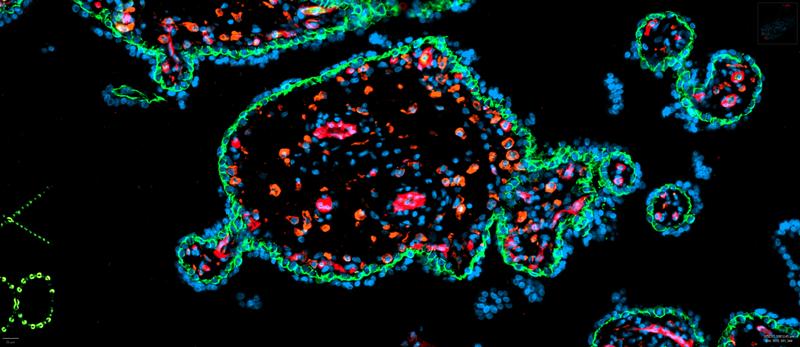

Ursachen und Mechanismen der Erkrankung sind noch weitgehend unklar. Als sicher gilt, dass die Plazenta und speziell deren Hofbauerzellen wesentlich daran beteiligt sind. Hofbauerzellen gehören zu den Makrophagen – weiße Blutzellen, die durch den Körper zirkulieren und Krankheitserreger beseitigen. „Studien an Tiermodellen zeigen, dass die klinischen Symptome sofort verschwinden, sobald die Plazenta entfernt ist“, erklärt PD Dr. Florian Herse. Er forscht in der Arbeitsgruppe „Hypertonie vermittelte Endorganschäden“ von Professor Dominik N. Müller und Professor Ralf Dechend am Experimental and Clinical Research Center (ECRC), einer gemeinsamen Einrichtung des Max Delbrück Center und der Charité – Universitätsmedizin Berlin.

Martin Gauster und sein Team haben ein Durchfluss-Kulturmodell für Plazentagewebe entwickelt, mit dem verschiedene Gesundheitszustände während der Schwangerschaft simuliert werden können. Mit Hilfe von Einzelzell-Sequenzierungen und mikroskopie-geleiteter Proteomanalysen untersucht und vergleicht Florian Herse in Berlin zusammen mit der Forschungsgruppe von Dr. Fabian Coscia die räumliche und zeitliche Dynamik der Makrophagen-Entwicklung in gesundem und erkranktem Plazentagewebe.

Hofbauerzellen zirkulieren nicht frei durch die Blutgefäße, sondern bleiben im fetalen Bereich der Plazenta. Dort scheinen sie zu verhindern, dass Krankheitserreger aus dem Blut der Mutter auf das Ungeborene übergehen. Bei Schwangerschaften, in denen es zu einer schweren Präeklampsie kommt, ist die Anzahl dieser Zellen verringert. „Wir vermuten, dass sie dadurch die Struktur der Gefäße und des umgebenden Gewebes verändern und so die Funktion der Plazenta beeinträchtigt wird“, sagt Florian Herse. „Deshalb wollen wir uns nun das Zusammenspiel der Makrophagen mit den Blutgefäßen genauer ansehen.“